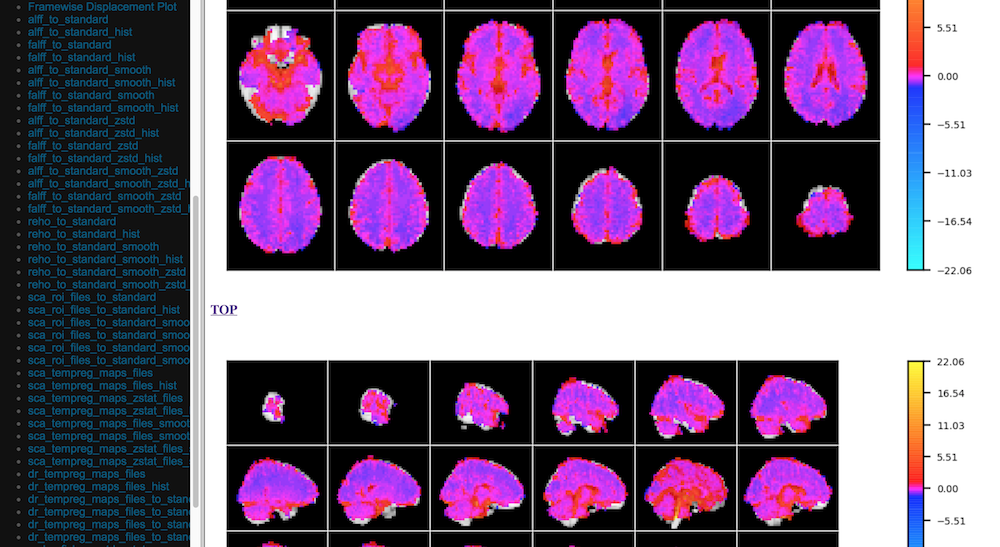

Quick View of Derivatives

../_images/qc_interface3.png

With Histograms

../_images/qc_interface4.png